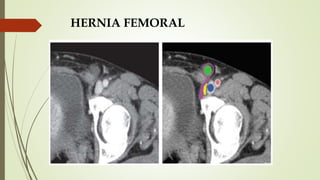

HERNIA FEMORAL

 HALLAZGOS DE TC:

 Mejor prueba de imagen.

 Grasa epiploica o intestino se hernian hacia el canal

femoral mediales a la vena femoral.

 Saco herniario posterior al plano horizontal del

tubérculo del pubis.

 HALLAZGOS DE ECOGRAFÍA

 Doppler color.

 Se identifica el saco herniario que se extiende medial a la

vena femoral.